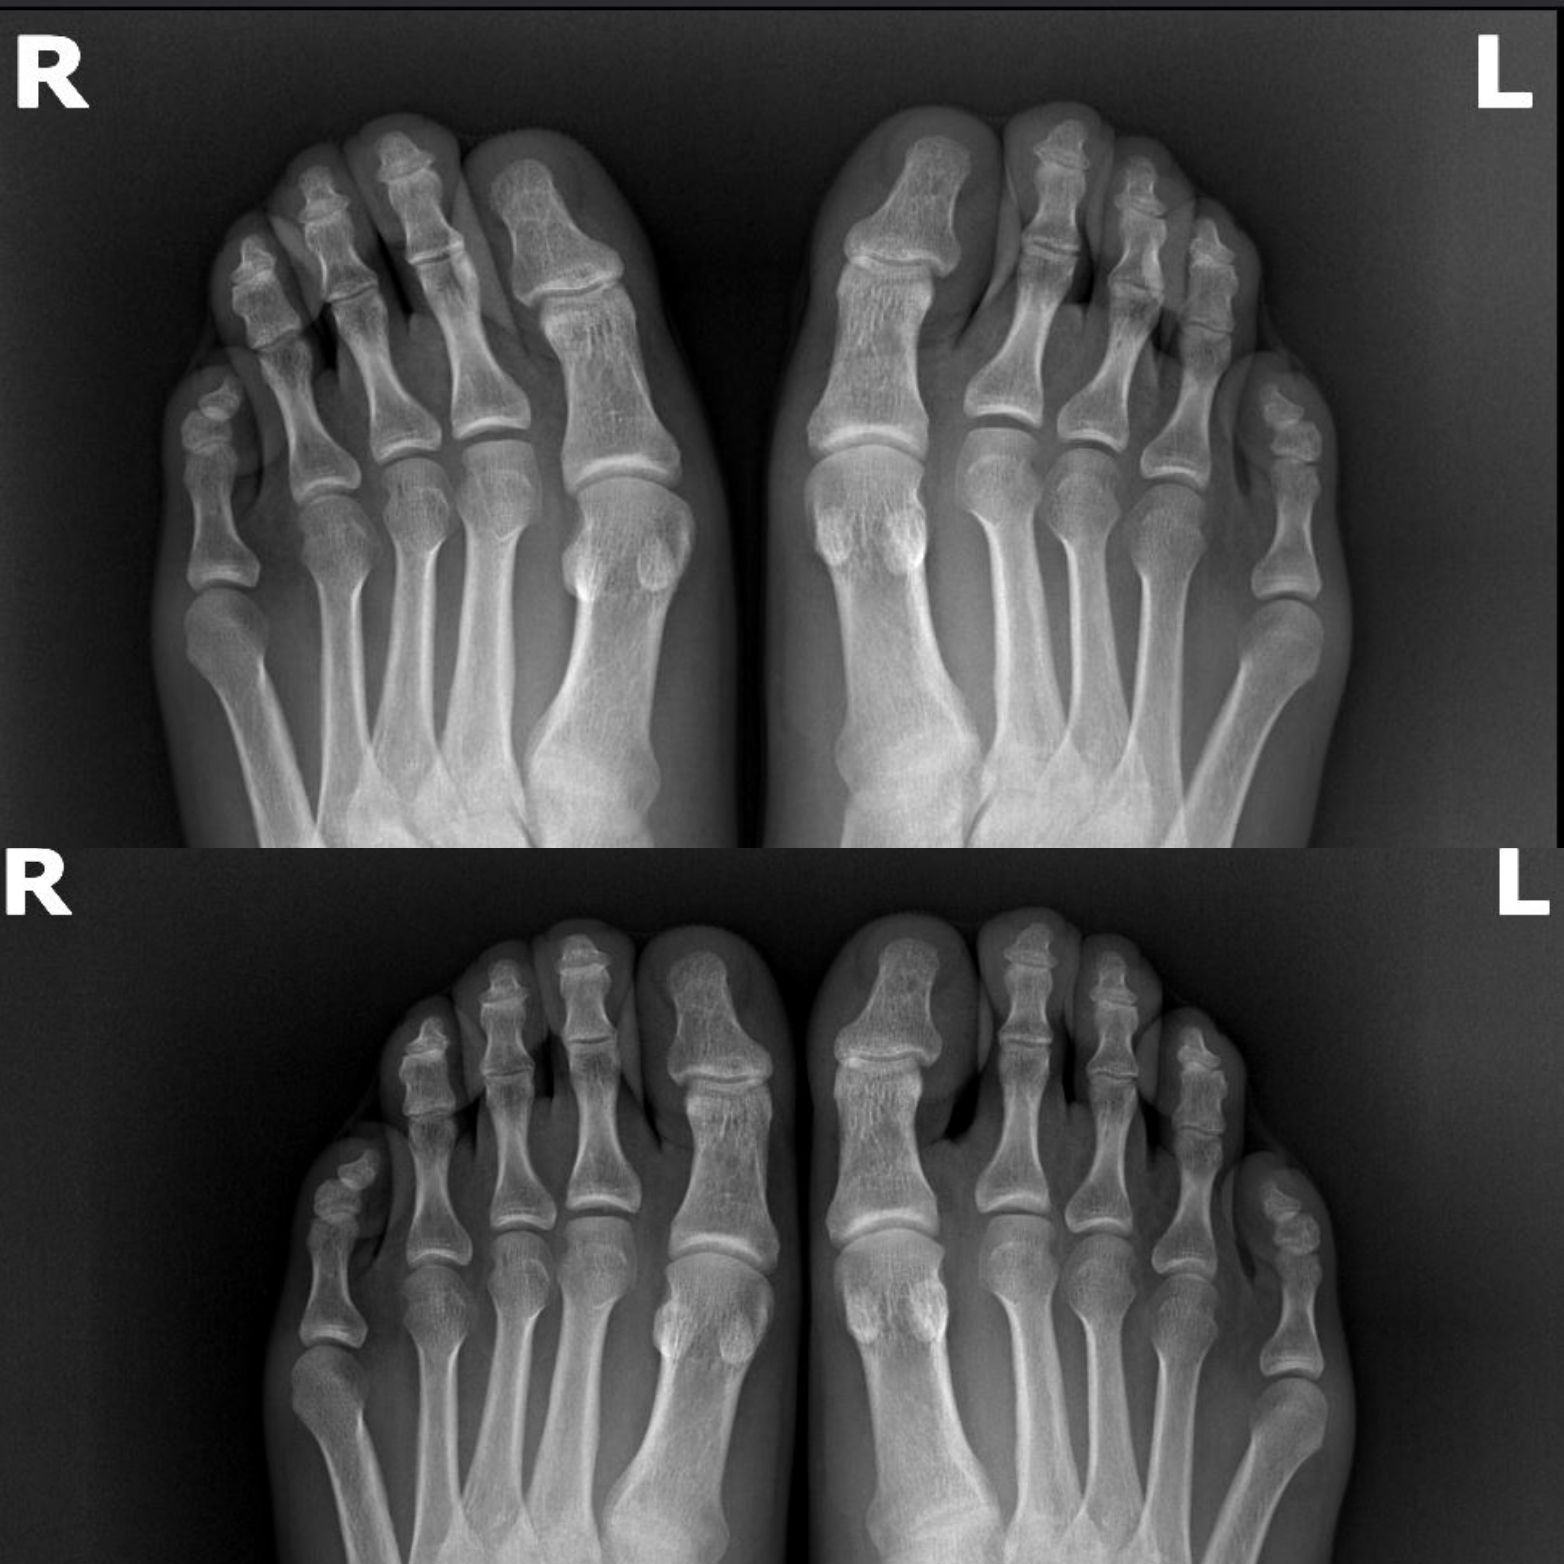

제가 이 일을 하면서 가장 많이 깨달은 점은 만성 통증과 불균형의 근본 원인이 발의 부정렬에서 시작된다는 사실입니다. 많은 재활 치료와 필라테스, 도수치료가 실패하는 이유는 가장 중요한 순서를 지키지 않기 때문입니다. 체형 교정의 순서는 다음과 같습니다:

- 발 교정: 발의 정렬이 제대로 잡히지 않은 상태에서는 어떤 운동도 효과를 보기 어렵습니다. 발은 몸 전체를 지탱하는 기초입니다.

운동과 함께 발의 정렬을 잡는 교정 솔루션을 병행하면 더욱 빠르고 확실한 효과를 볼 수 있습니다. 고객님께서는 운동 후 **오소틱(교정용 깔창)**을 착용하신 뒤, 바른 걸음 훈련을 진행하셨고, 결과적으로 허리가 펴지고 자연스럽게 앞을 보며 걷게 되셨습니다.